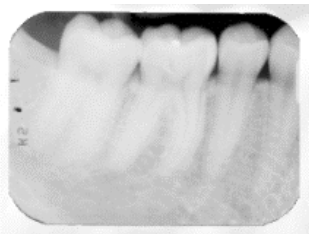

Analise a radiografia a seguir.

Não contribui para esse possível erro radiográfico: